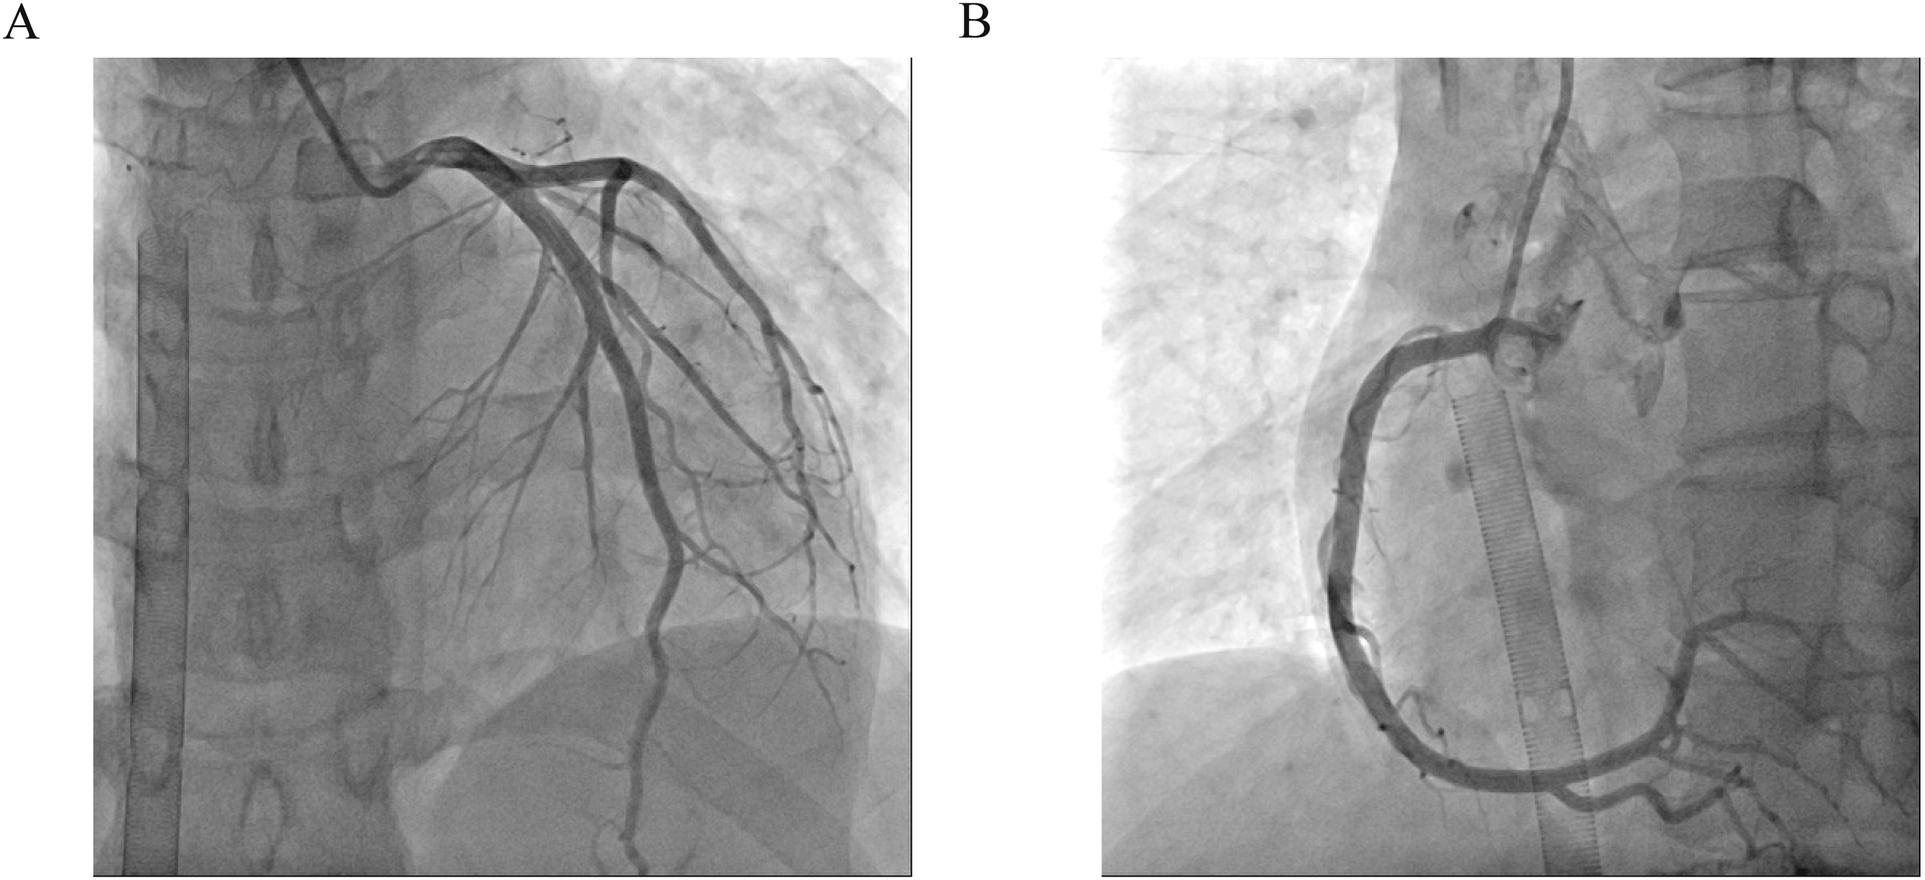

One day after admission, the patient's vital signs were unstable and her blood pressure remained low despite high doses of norepinephrine and m-hydroxyamine. Physical examination revealed scattered red maculae and maculopapules on the trunk and limbs, accompanied by iridoid lesions, blisters, and oral mucosal erosion (Figure 2). Echocardiography examination indicated a significant decrease in Ejection fraction (24%). A review of laboratory tests showed: WBC 6.6 × 109/L, CRP 20.2 mg/L, ALT 225 U/L, LDH 658 U/L, cTnI 20.9 ng/ml, CK 803 U/L, Lactate 6.62 mmol/L, NT-proBNP 6,690 ng/L. Considering the risk of cardiac arrest remains high, endotracheal intubation, V-A ECMO, and emergency coronary angiography were performed. Coronary angiography showed no obvious coronary vessel stenosis (Figure 3). At the same time, we performed extensive hematological tests to determine the cause of the erythema multiforme. Blood cultures were negative for bacteria and fungi. Immunological tests such as antinuclear antibodies, anti-double-stranded DNA antibodies and rheumatoid factors were negative. COVID-19 polymerase chain reaction was negative. HIV, Hep A, B, C and Treponema pallidum serologies were negative. Coxsackie virus, adenovirus, influenza A virus, influenza B virus, human parainfluenza virus, respiratory syncytial virus, Mycoplasma pneumoniae, chlamydia pneumoniae were negative. However, Chemiluminescence showed that herpes simplex virus-1 (HSV-1) was positive. Therefore, we considered that the patient had severe myocarditis and erythema multiforme due to infection with HSV-1 virus. We gave acyclovir needle antiviral and methylprednisolone needle anti-inflammatory. After the initiation of ECMO, the patient's blood pressure significantly increased and gradually stabilized at a systolic blood pressure of 90–168 mmHg and a diastolic blood pressure of 64–112 mmHg. Arterial blood gas analysis showed a significant improvement in acidosis. Therefore, we discontinued all vasoactive medications on the second day following the initiation of ECMO. Four days after the initiation of ECMO, the flow rate was reduced to 1.2 L/min, the patient's blood pressure remained relatively stable, blood gas analysis indicated good tissue perfusion, and follow-up echocardiography showed that the ejection fraction (EF) had recovered to 42%. We concluded that the criteria for ECMO withdrawal had been met, and ECMO was removed four days after its initiation. The day after ECMO was removed, the patient was then scheduled for a cardiac magnetic resonance imagery (CMRI) examination. Cardiac magnetic resonance T2-weighted imaging shows diffuse hypersignal in the left ventricular wall (Figure 4). Finally, the patient's symptoms gradually improved, the rash gradually disappeared on the seventh day, and she was discharged successfully after 2 weeks of treatment. The specific clinical process is shown in Supplementary Image 1. The patient has now been under observation for a period of one year, during which time she has attended five outpatient reviews at the hospital. No significant abnormalities have been observed in the patient's skin, troponin levels, electrocardiogram, or cardiac ultrasound. Furthermore, the patient has not continued any medications for the treatment of ring erythematosis or myocarditis.

Figure 3

Coronary angiography. (A) Left coronary artery showed no obvious coronary vessel stenosis. (B) Right coronary artery showed no obvious coronary vessel stenosis.

Myocarditis, one of the most important diseases of cardiovascular disease, used to have an incidence of 1 to 10 cases per 100,000 people per year (9). The highest risk was found in people aged 20 to 40 (10). Myocarditis can be caused by a variety of infectious and non-infectious causes. In infectious myocarditis, viruses are the most common cause. Viral myocarditis can be caused by adenovirus, enterovirus, COVID-19 and other viruses, but HSV-1 virus caused myocarditis is extremely rare. Bowles et al. used polymerase chain reaction (PCR) to analyze viral genomes in heart tissue and blood to identify common viral causes of myocarditis in different age groups. The viral genome was amplified in 239 (38%) of 624 patients with myocarditis, of which HSV infection accounted for only 0.8% of myocarditis (5). Previous basic studies have shown that myocarditis caused by HSV-1 infection is regulated by members of the TRIM protein family. TRIM29 could regulate the innate immunity to promote DNA virus HSV-1 infection (11) and loss of TRIM29 mitigates viral myocarditis by attenuating PERK-driven ER stress immune response (12). Additionally, TRIM18 deficiency is reported to control DNA virus HSV-1 infection and viral myocarditis (13). In this case, although acute myocardial infarction caused by coronary artery occlusion was excluded by coronary angiography, and myocarditis was diagnosed by troponin, magnetic resonance, and echocardiography, it was still difficult to diagnose the cause of myocarditis. The occurrence of multitype erythema provides the basis for the diagnosis of viral myocarditis and the direction for the targeted virus screening.